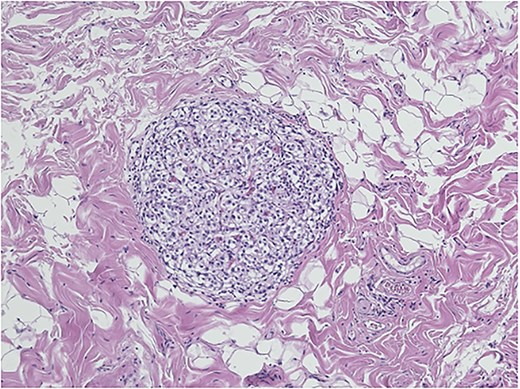

Histopathological analysis of the gallbladder demonstrated follicular cholecystitis along with an incidental paraganglioma (Fig. 4). This lesion showed positivity with CD56, synaptophysin, and chromogranin staining with admixed S100-positive sustentacular cells (Fig. 5). Keratin was negative.

Gallbladder paraganglioma with characteristic Zellballen pattern seen in hematoxylin and eosin, ×20.